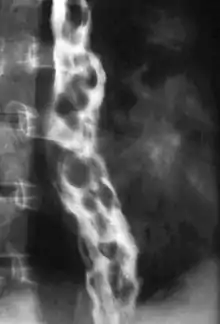

The upper two thirds of the esophagus are drained via the esophageal veins, which carry deoxygenated blood from the esophagus to the azygos vein, which in turn drains directly into the superior vena cava. These veins have no part in the development of esophageal varices. The lower one third of the esophagus is drained into the superficial veins lining the esophageal mucosa, which drain into the left gastric vein, which in turn drains directly into the portal vein. These superficial veins (normally only approximately 1 mm in diameter) become distended up to 1–2 cm in diameter in association with portal hypertension.

Normal portal pressure is approximately 9 mmHg compared to an inferior vena cava pressure of 2–6 mmHg. This creates a normal pressure gradient of 3–7 mmHg. If the portal pressure rises above 12 mmHg, this gradient rises to 7–10 mmHg.[5] A gradient greater than 5 mmHg is considered portal hypertension. At gradients greater than 10 mmHg, blood flowing through the hepatic portal system is redirected from the liver into areas with lower venous pressures. This means that collateral circulation develops in the lower esophagus, abdominal wall, stomach, and rectum. The small blood vessels in these areas become distended, becoming more thin-walled, and appear as varicosities.

In situations where portal pressures increase, such as with cirrhosis, there is dilation of veins in the anastomosis, leading to esophageal varices.[3] Splenic vein thrombosis is a rare condition that causes esophageal varices without a raised portal pressure. Splenectomy can cure the variceal bleeding due to splenic vein thrombosis.

Varices can also form in other areas of the body, including the stomach (gastric varices), duodenum (duodenal varices), and rectum (rectal varices). Treatment of these types of varices may differ. In some cases, schistosomiasis also leads to esophageal varices.